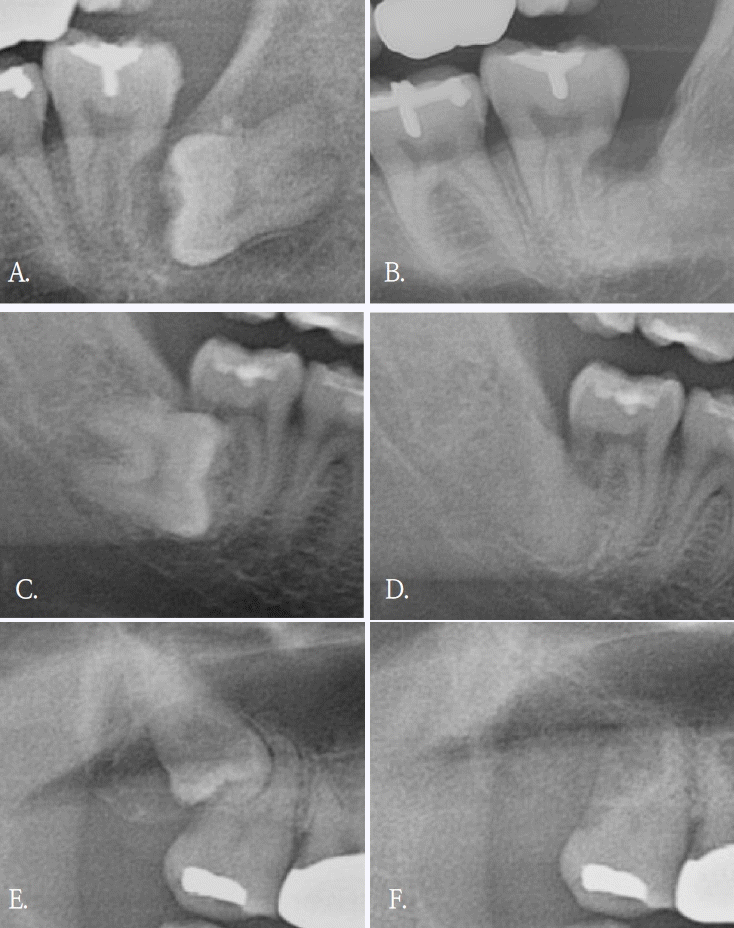

Figure 1.

Bony healing and dentin bridge formation is visible on post operative panoramic radiographies (B, D, and F) compared to preoperative panoramic radiographies (A, C, and E). A. Pre-operative panoramic radiograph of left lower third molar. B. Panoramic radiograph of left lower third molar after 11 months of surgery. C. Pre-operative panoramic radiograph of right lower third molar. D. Panoramic radiograph of right lower third molar after 14 months of surgery. E. Pre-operative panoramic radiograph of right upper third molar. F. Panoramic radiograph of right lower third molar after 11 months of surgery.